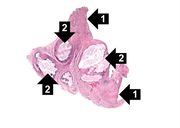

| 15:18, 20 August 2013 | IPLab5Gout3.jpg (file) | 21 KB | This is a low-power photomicrograph of the tophus removed from the elbow of this patient. Note the fibrous connective tissue (1) and the large foci containing the urate crystals (2) surrounded by the intense chronic inflammatory reaction. | 1 | |